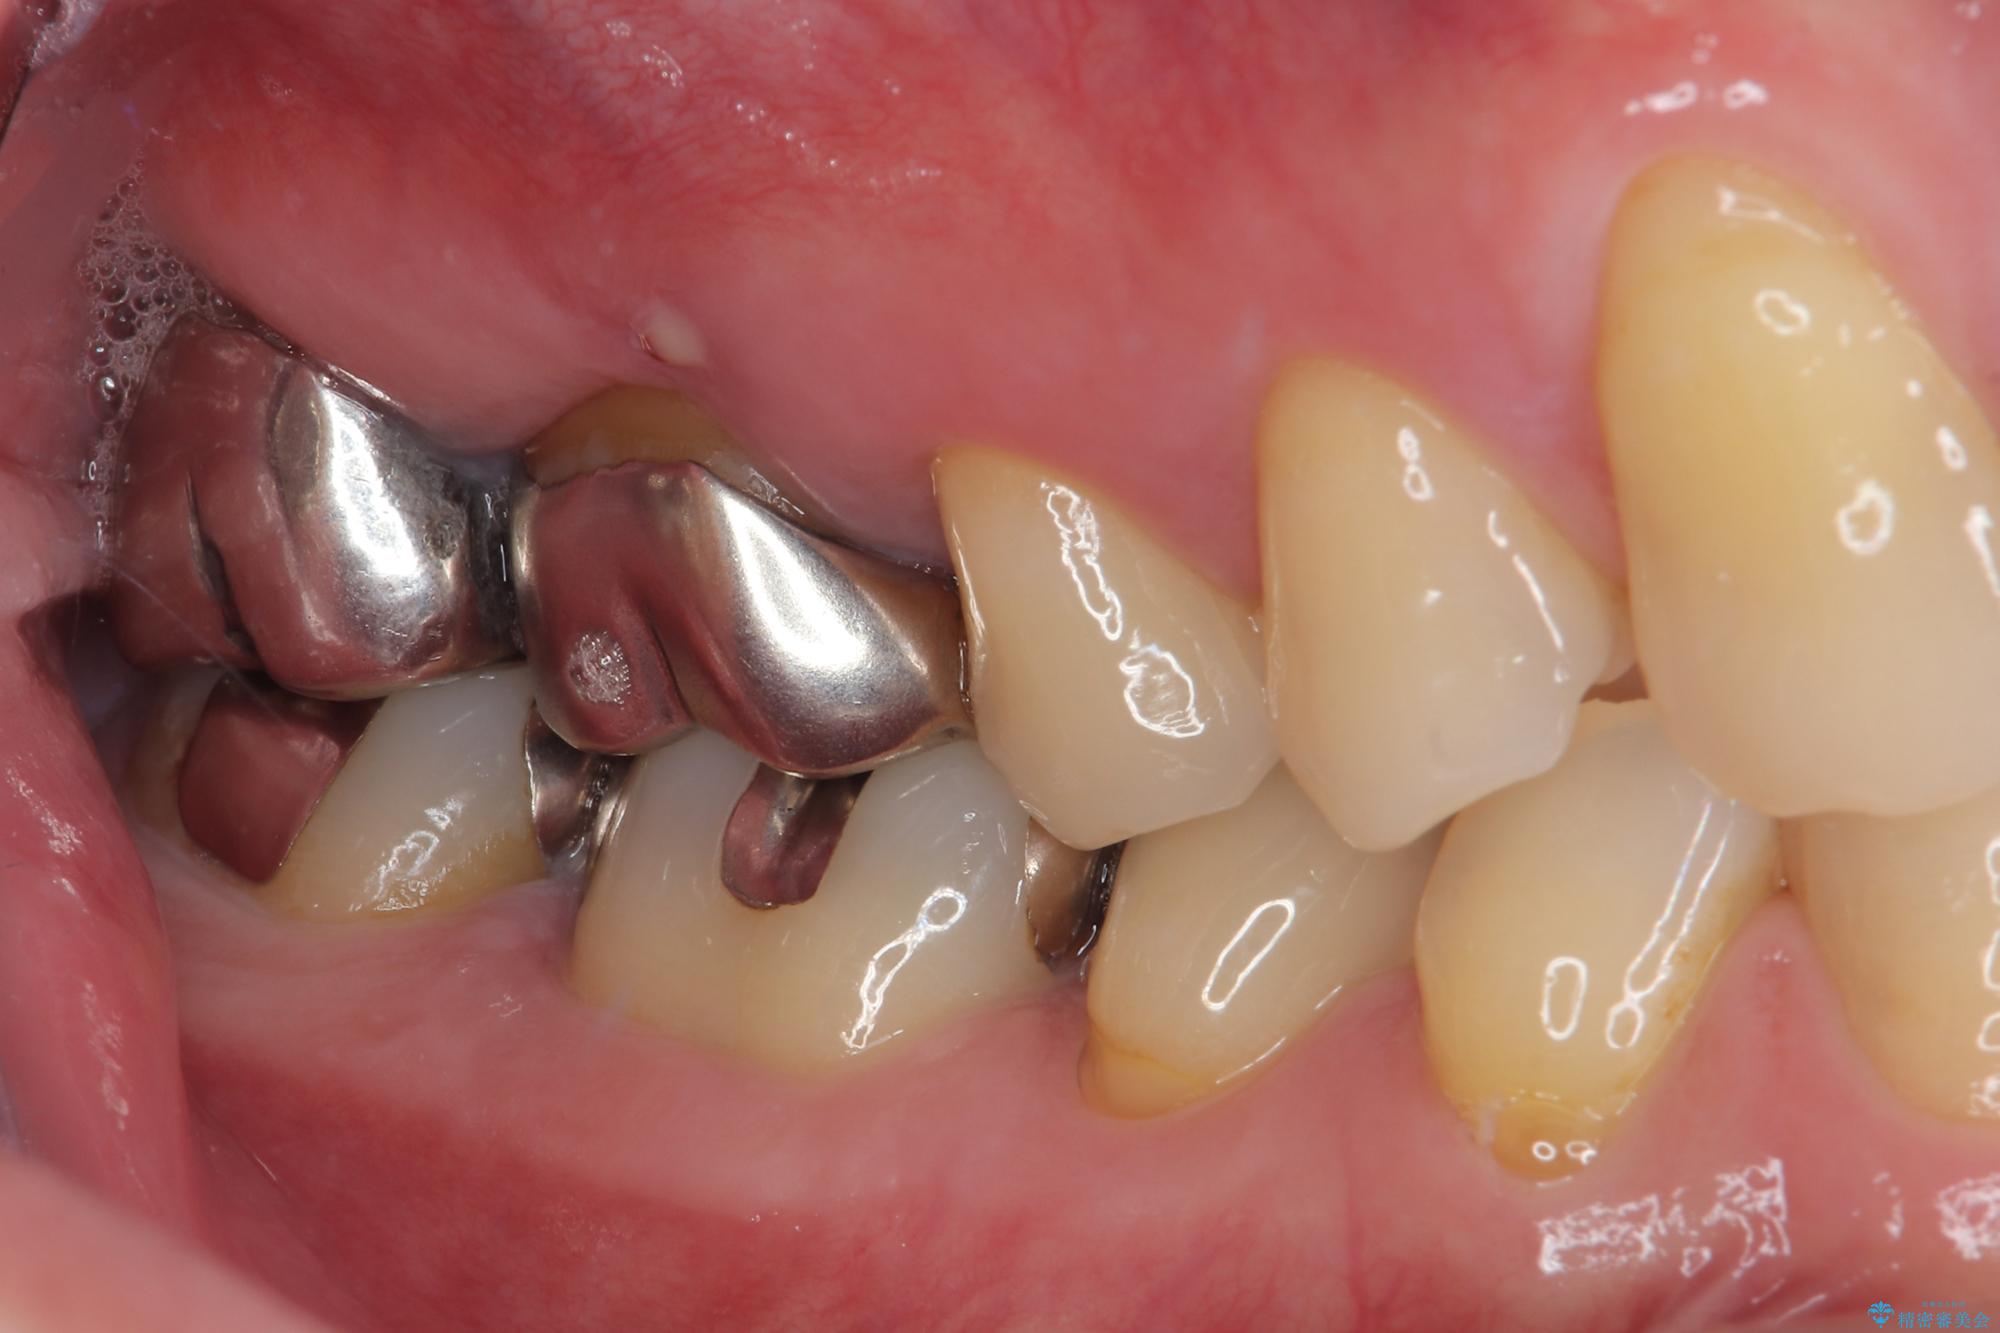

- 右下の銀歯が取れたとのことで来院された患者様です。以前にも取れていたところで、メタルインレーの不適合も認めていたため、次回外れたらオールセラミッククラウンにやり替えていくことを説明していたため、オールセラミッククラウンによる補綴治療を行っていくことにしました。